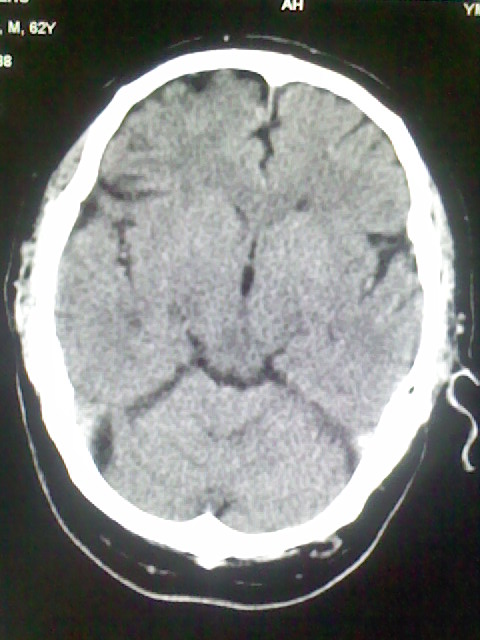

标题: CT15555:头痛 10余日 来诊大家帮忙看看

脑萎缩

脑沟、裂增宽,提法脑萎缩,建议mt检查。

脑萎缩,以小脑为著。

脑沟、裂增宽,提示脑萎缩

老年脑

支持轻度脑萎缩。